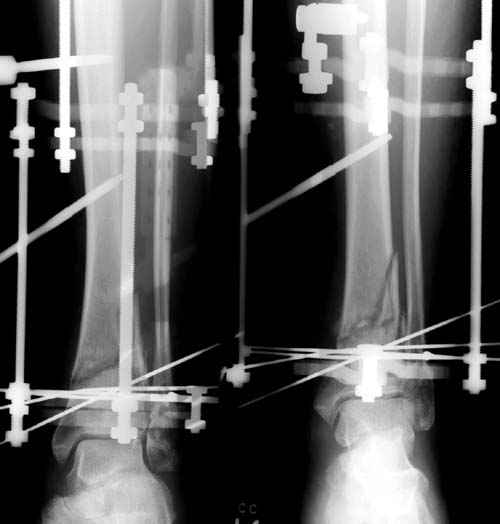

В то время метод Илизарова был на пике славы, и многие, как альтернативу пластинам, при внутри- и околосуставных переломах стали применять аппараты. Закрытая репозиция и возможности манипуляции мульти-направленными спицами в коротком отломке создавали преимущества перед другими методами.

Здесь представлены несколько примеров снимков с осложнением, медиальная пластина, медиальная в комбинации с латеральной, метод Илизарова, а также сравнительные данные толщины медиальных пластин Synthes 4.4 mm, DePuy 3.2 mm.